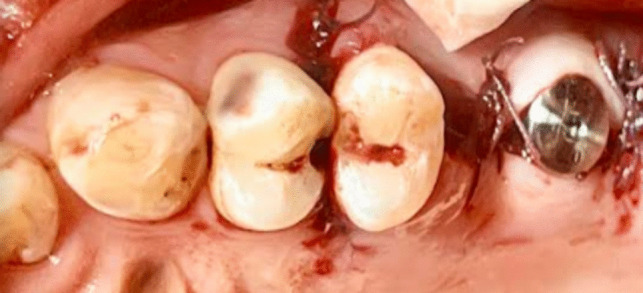

Materials and methods: A total of 30 sinuses with an average residual alveolar bone height ranging from 4-7 mm participated in this randomized controlled clinical trial. Following a closed sinus lift procedure, patients were randomized into two groups: one for the ozone gel recipient group and the other for control group. Cone beam computed tomography was carried out both immediately and four months postoperatively. Radiographic evaluations were performed to assess bone width and labial plate thickness at both crestal and midcrestal levels.

Abstract Image